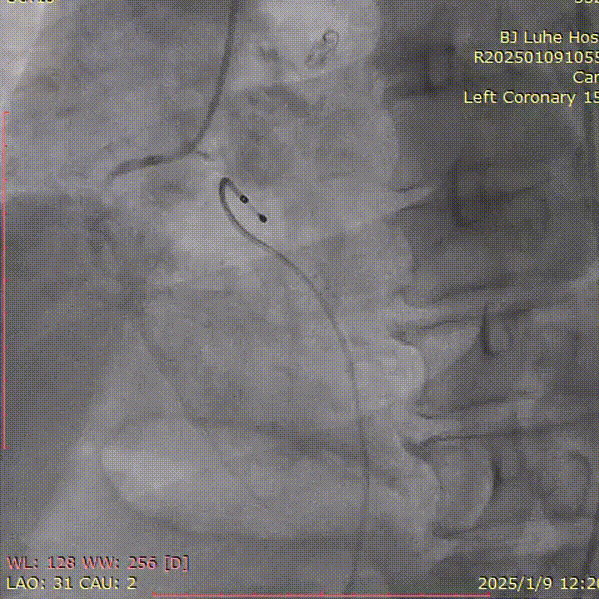

右冠造影

左冠造影

主动脉根部造影